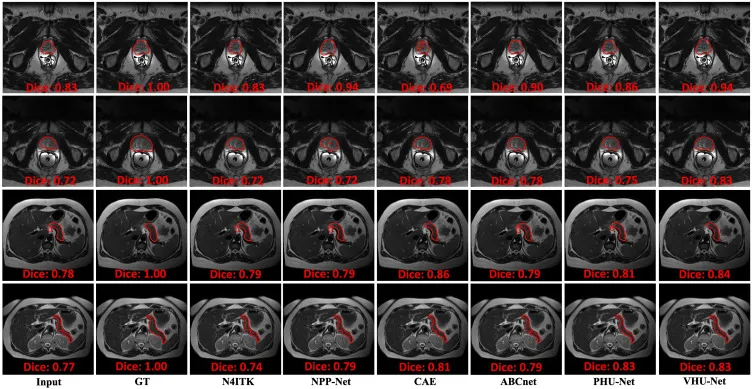

VHU-Net在合成和真实体部MRI数据集(腹部、前列腺、乳腺)上的综合实验表明其优于现有最先进的偏置场校正方法。在合成PanSegData数据集上,VHU-Net在SSIM、PSNR、COCO和CV等所有指标上均表现最佳,尤其在COCO分数上达到0.987,证明了其在模拟条件下的卓越性能。相比N4ITK,VHU-Net的CV降低了8.49%。在真实T2加权PanSegData数据集上,VHU-Net在CV指标上优于所有其他方法,相对N4ITK、ABCnet、NPP-Net、CAE和PHU-Net分别降低了7.20%、2.34%、4.47%、2.30%和3.15%,表明其对真实临床输入的有效泛化能力。在T1加权PanSegData数据集上也取得了最低的CV。在多中心前列腺MRI数据集上,VHU-Net在HK、BIDMC和RUNMC数据集上均表现出卓越的强度均匀性,证实了其跨域泛化能力。在乳腺MRI数据集上,VHU-Net在SSIM、PSNR、COCO和CV上均达到最佳,其估计的偏置场最接近真实值。消融研究证实了HT层、IHTRTB、平滑正则化、ELBO和半软阈值层以及超网络的有效性,每个模块的移除都导致性能下降。在下游分割任务中,VHU-Net作为偏置场校正方法,显著提高了TransUNet和nnUNetV2在前列腺和胰腺分割中的Dice、敏感性和PPV分数,尤其是在前列腺分割中,TransUNet的Dice分数从0.686提高到0.756。在计算效率方面,VHU-Net表现出接近实时的推理速度,比N4ITK快100多倍,并在处理速度和校正精度之间取得了良好的平衡。

图14分割实验的定性结果。